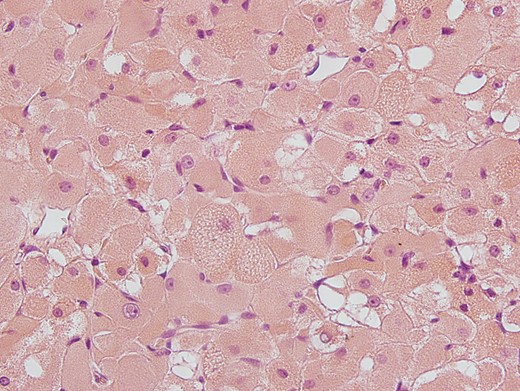

A 65-year-old male was referred to our department with a constant urge to clear the throat for a time span of 12 months. In addition, the patient stated his progressing inability to swallow food. Due to these symptoms, a resection of the thyroid gland had been carried out earlier showing struma colloides nodosae as well as bilateral parathyroidal adult rhabdomyomae. Even so, there was no relief in symptoms. At outpatient presentation at his dentist, a slight swelling of the soft palate was felt and the patient was referred for further therapy. Endoscopic examination as well as magnetic resonance imaging (MRI; Fig. 1) unveiled a tumor on the right side of the soft palate with a size of 5 × 5 cm2 and distinct demarcation to the surrounding tissue. Subsequently, the lesion was completely excised (Fig. 2) and histopathological analysis was conducted that showed a circumscribed but not encapsulated mesenchymal tumor with polygonal cell formation. The cells presented a granular cross-striated eosinophilic cytoplasm, large round vesicular nuclei and so called spiderweb cells (Fig. 3). Immunohistochemically, the cytoplasm of the cells was 100% positive for antibodies to desmin and S100 (Fig. 4). Additional immunohistochemical markers showed slight nuclear positivity for myogenin and nuclear negativity for AE1/3, CD68 as well as melan A. The histological examination confirmed ARM without signs of malignancy. At a total follow-up of 3 years, including MRI scan, no signs of recurrence were detected.

Hematoxylin-eosin (H&E) staining: polygonal cell formation with granular cross-striated eosinophil cytoplasm and large round vesicular nulei are seen.